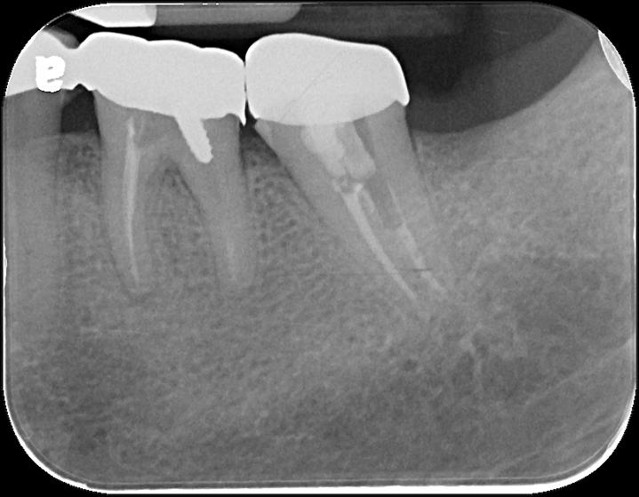

治療前,左下第二大臼齒根管鈣化

顯微根管治療